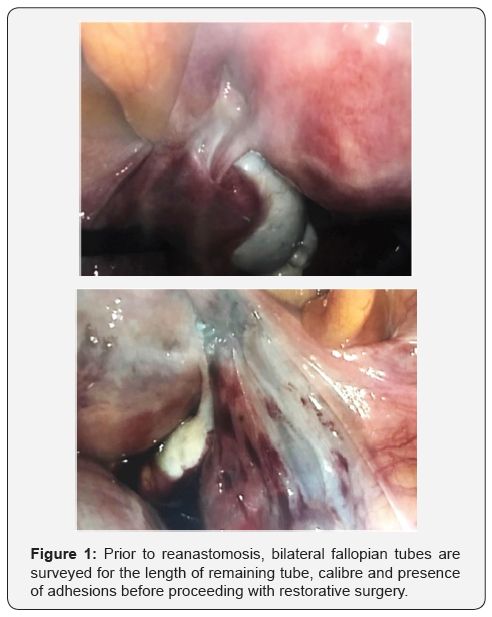

We present the case of 34-year-old multiparous woman who underwent reversal of tubal ligation and subsequently delivered a livebirth from a spontaneous conception. Our patient was a 34 year-old woman who was recently remarried and trying to conceive. Her obstetric history included four term normal vaginal deliveries from her previous partner, and two early miscarriages. After her last delivery four years ago, she underwent postpartum sterilization. This was performed with tubal occlusion using non absorbable titanium and silicon rubber clips (Filschie® clips) via a minilaparotomy (Figures 1) [1].

She underwent laparoscopic reversal of tubal ligation and tubal re-anastomosis under general anaesthesia. Routine laparoscopic Veress entry was achieved and the status of her tubes was evaluated. Both Filschie® clips were removed with careful dissection. Methylene blue was use to identify the proximal and distal tubal lumens via hydrotubation and tubal cannulation.